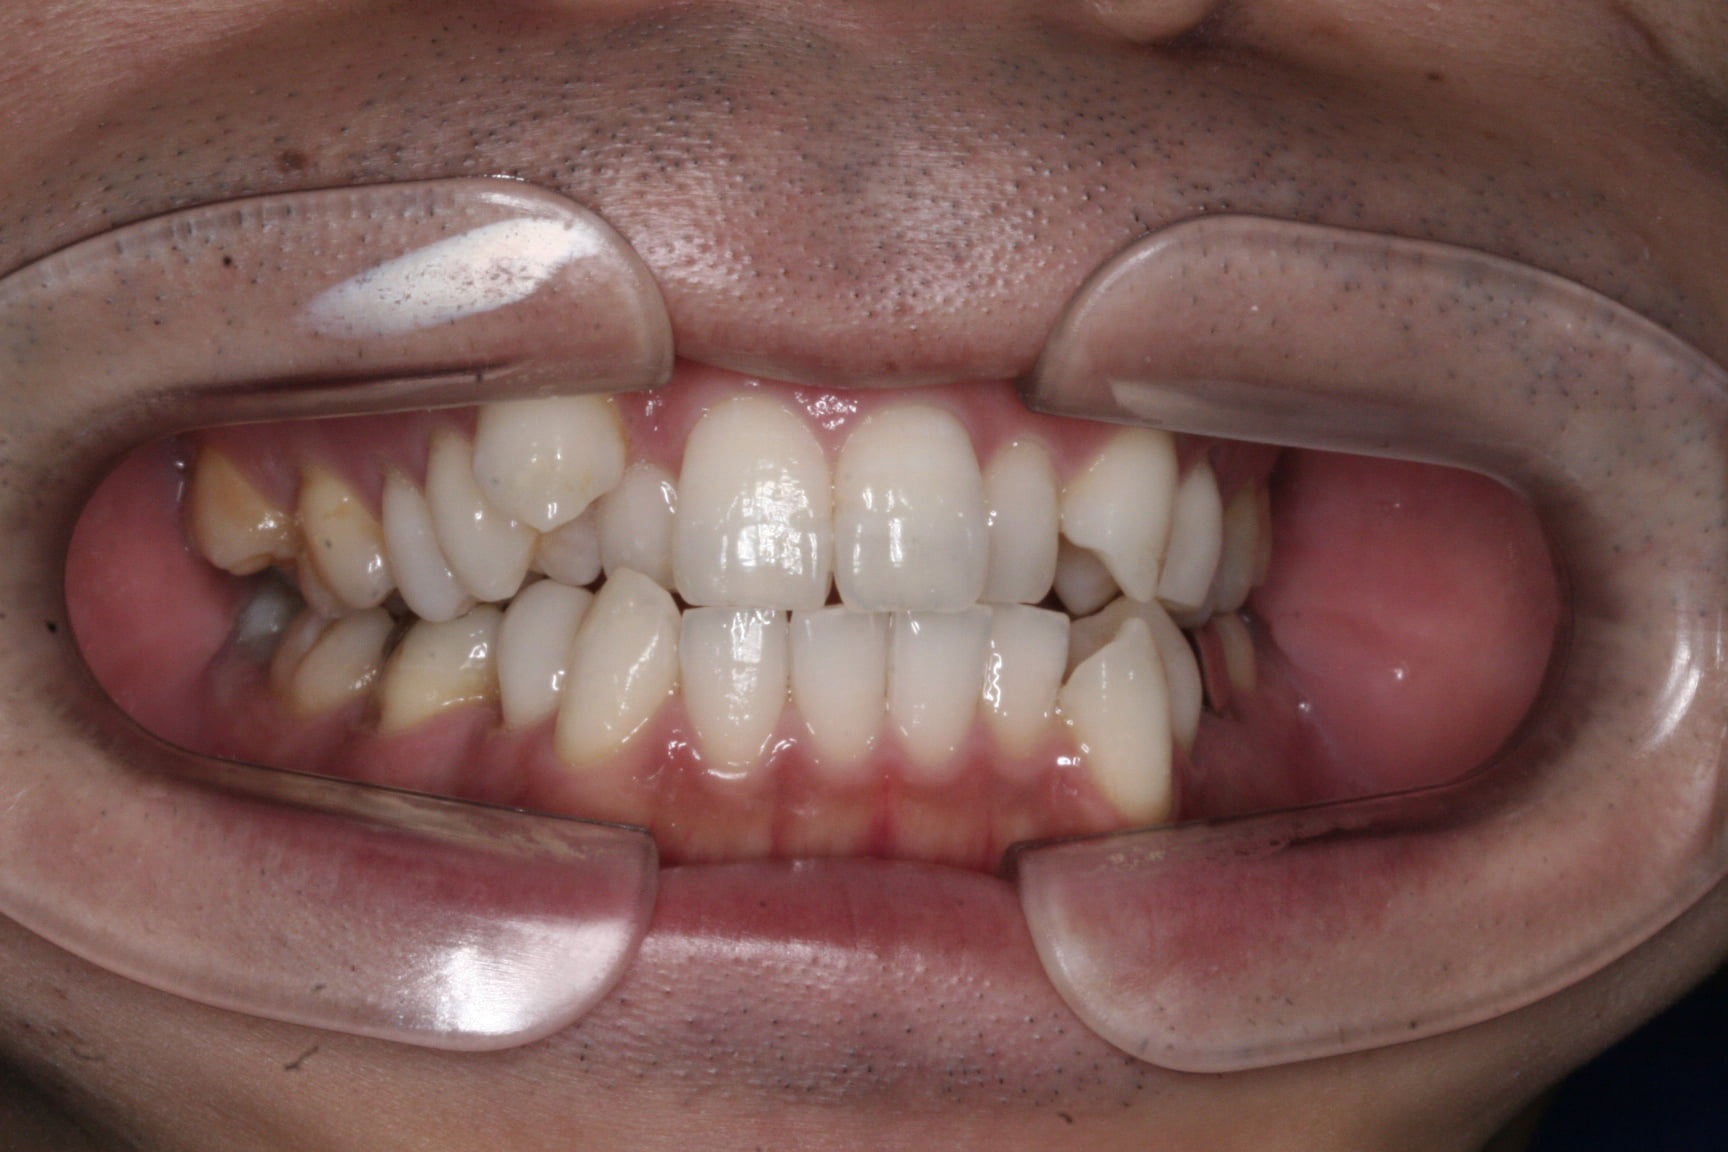

八重歯を改善したい

年齢層 20代

性別 女性

主訴 【主訴】凸凹を治したい 【診断・症状】叢生・上下顎劣成長・交叉咬合・下顎右方偏位

治療費用 検査・診断:38,500-/表側矯正治療:1,155,000-(※全て税込)

治療期間 約2年10か月(34回)

抜歯 抜歯:有(上4,4・下5,5)

矯正の装置 表側矯正

副作用、リスク 歯肉退縮・歯根吸収・疼痛・咬合の違和感・装置の違和感・正中のズレ

初診

Before

終了時

After